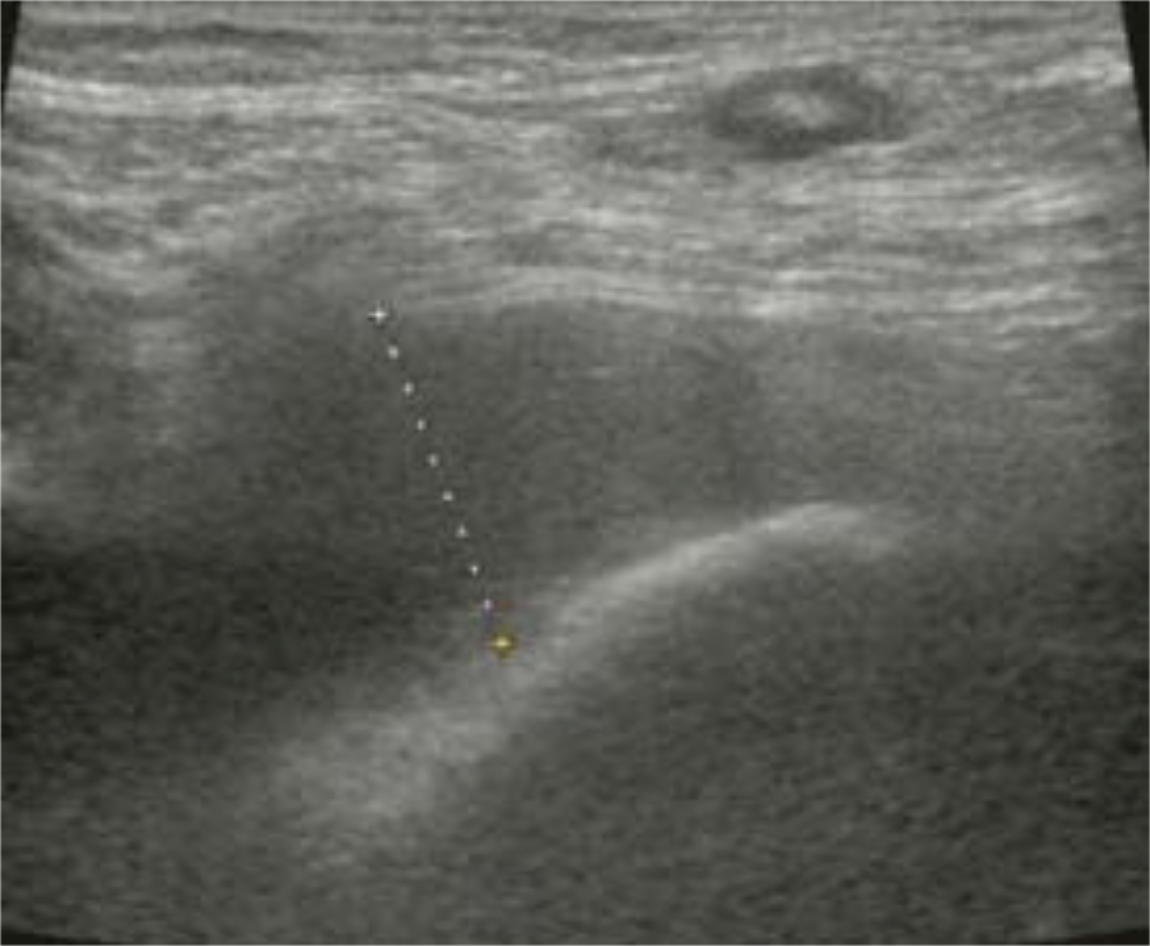

She was reviewed 2 years later and found to have no pain, a normal range of hip motion, and able to fully weight-bear without supporting aids, but she had a clicking and clunking sensation during index hip flexion moment 23 months postoperatively. At the same time, she noticed a soft tissue mass in her right inguinal region. Inflammatory serology was normal. The serum cobalt and chromium ion levels were 2.4 ng/ml and 0.05 ng/ml, respectively. Plain radiographs did not show any impending implant failure, but calcar osteolysis was visible (Figure 1). An ultrasound scan (APLIO XG SSA-790A PLT-805AT, Toshiba Medical Systems Corp., Tokyo, Japan) showed a mixed fluid and solid mass (Figure 2).

Figure 2 :Ultrasound scan, lateral to anterior, of the hip in Case 1, demonstrating a mixed fluid and solid mass.